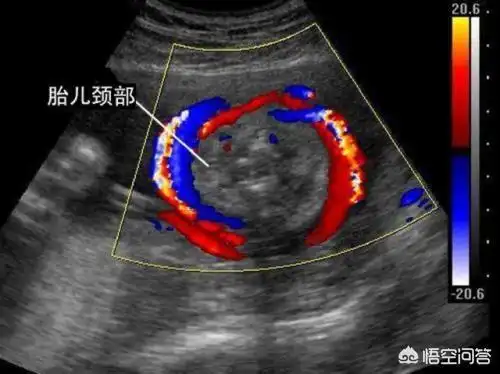

脐带绕颈两圈 一周成功绕出!

胎儿颈部可见u型压迹什么意思

胎儿脐带绕颈,看胎儿的b超图像,胎儿的颈部会有u型压迹,超声提示会

胎儿颈部可见u型压迹,到底是怎么一回事呢?

分钟前 医生来自冠县人民医院 答: 超声报告显示胎儿颈部u型压迹